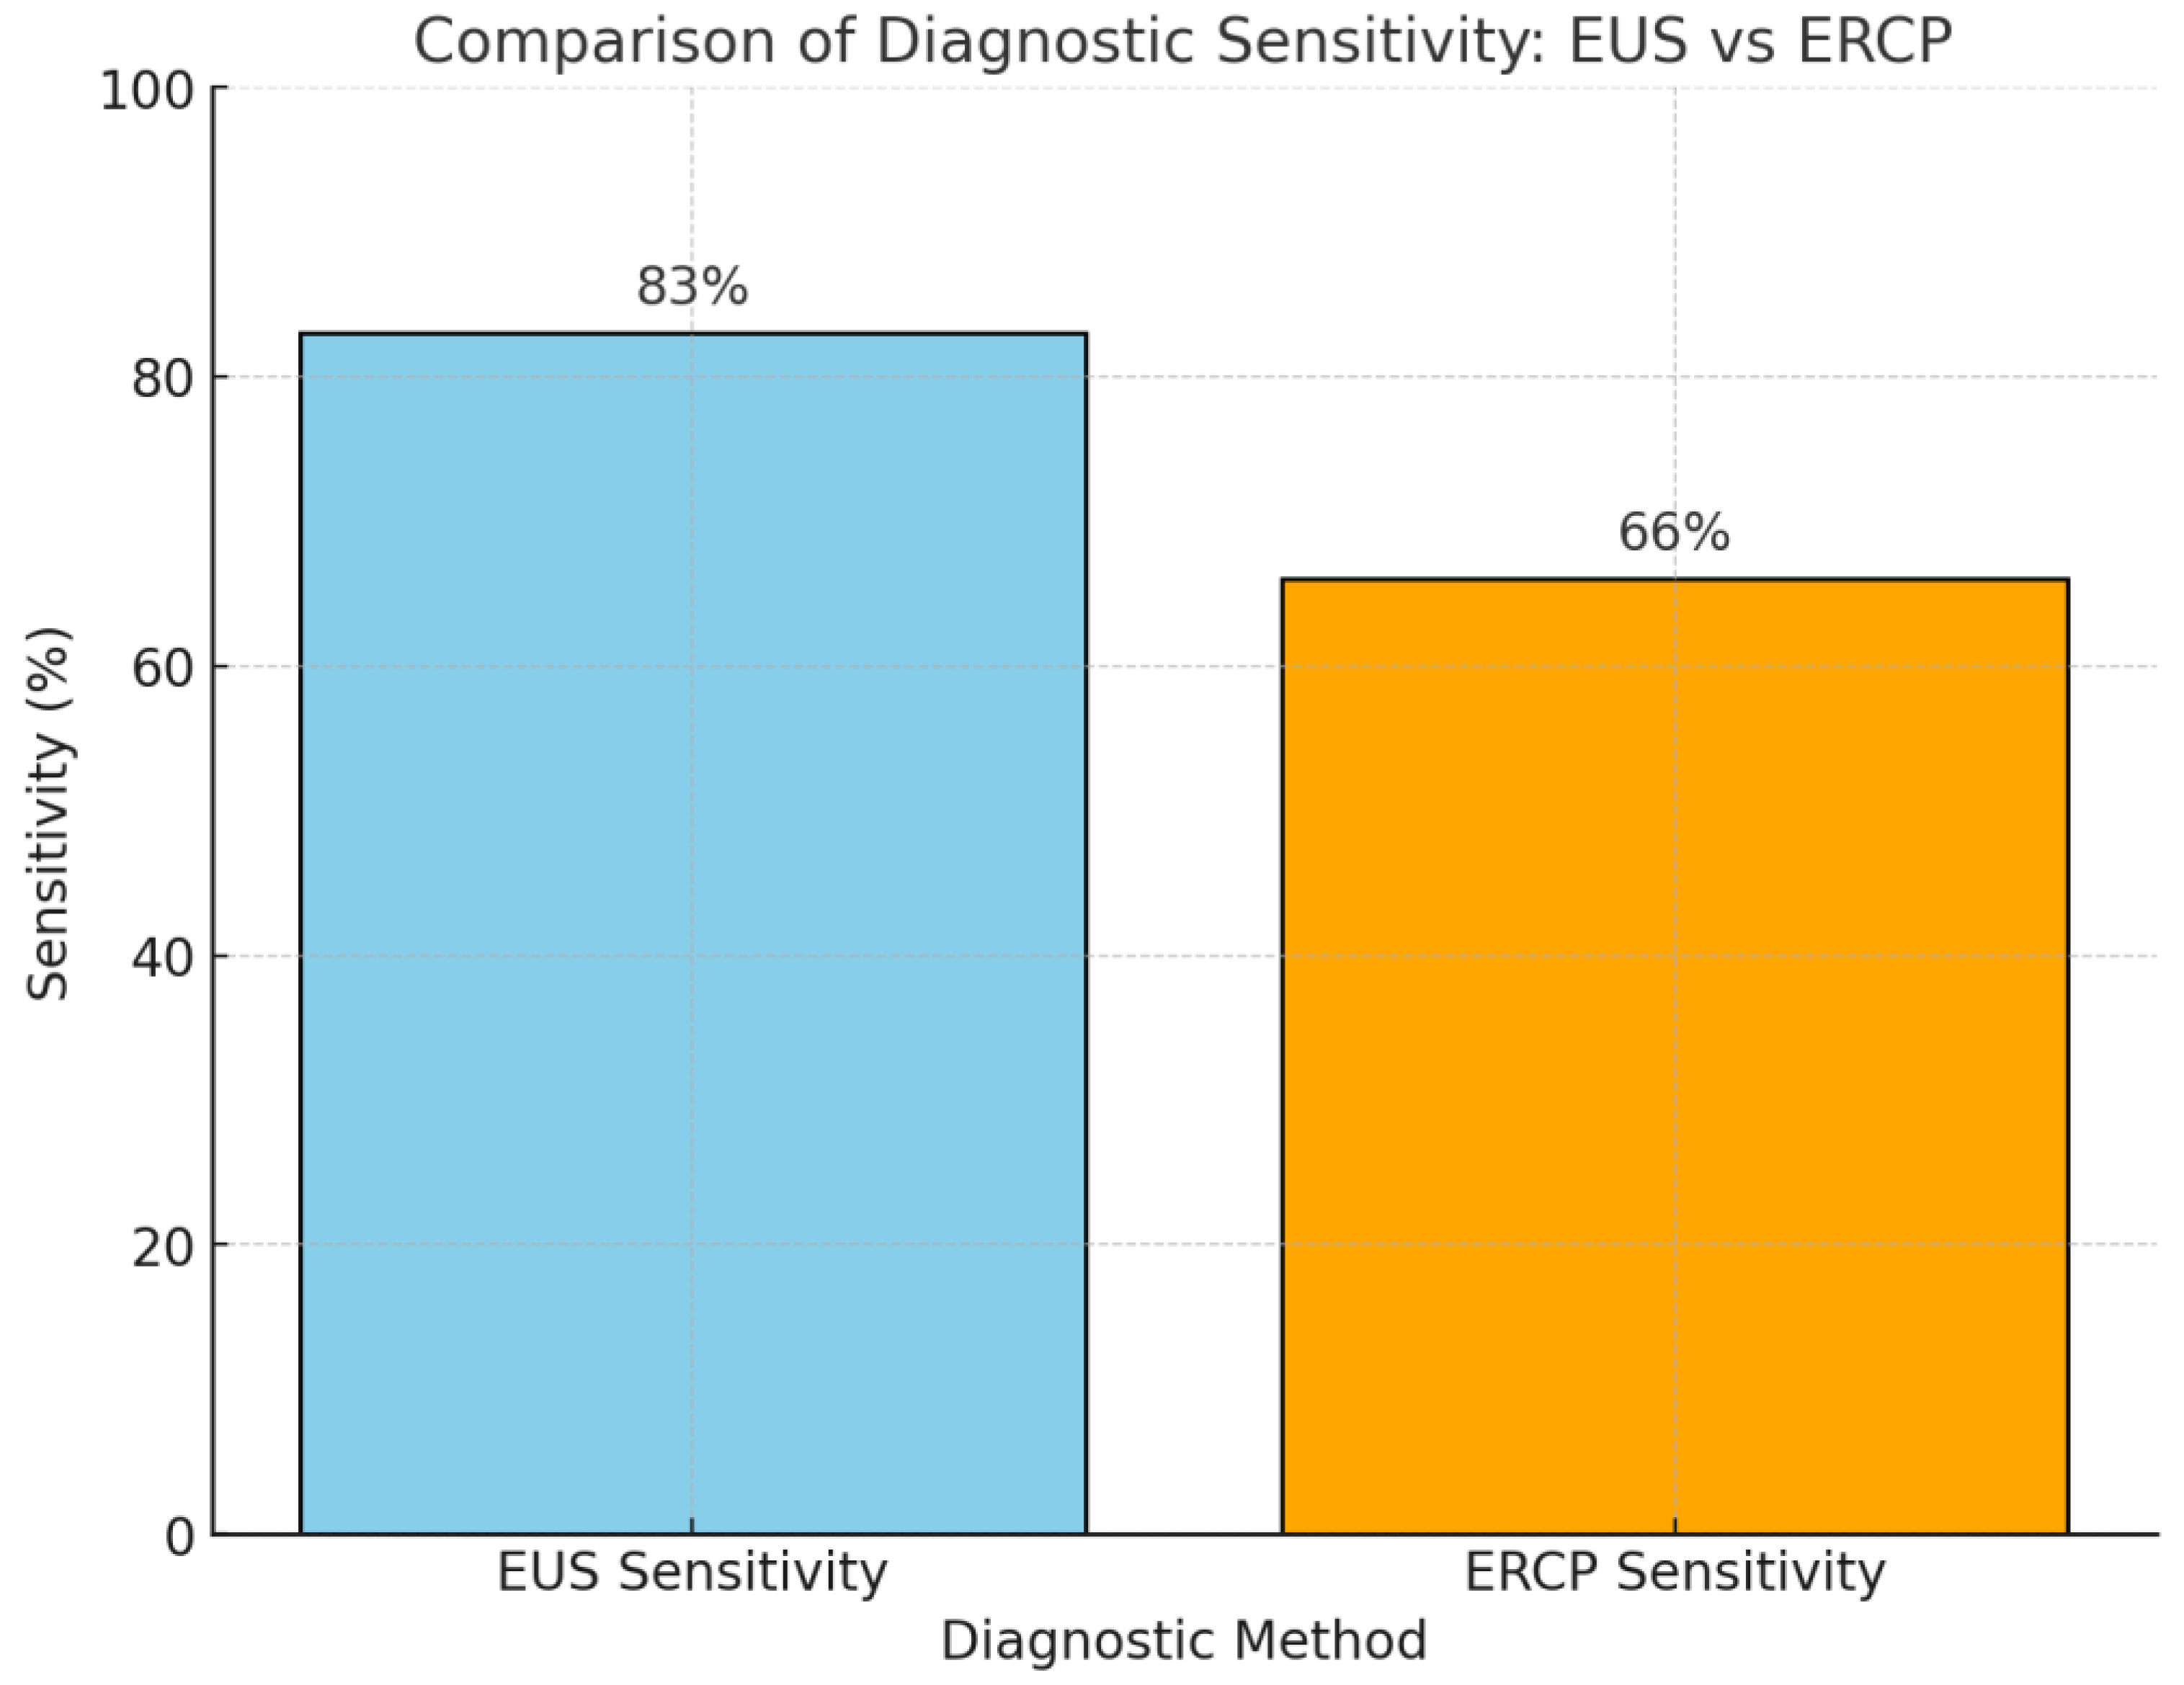

- Weilert, F.; Bhat, Y.M.; Binmoeller, K.F.; Kane, S.; Jaffee, I.M.; Shaw, R.E.; Cameron, R.; Hashimoto, Y.; Shah, J.N. EUS-FNA is superior to ERCP-based tissue sampling in suspected malignant biliary obstruction: Results of a prospective, single-blind, comparative study. Gastrointest. Endosc. 2014, 80, 97–104. [Google Scholar] [CrossRef]

- Chiang, A.; Theriault, M.; Salim, M.; James, P.D. The incremental benefit of EUS for the identification of malignancy in indeterminate extrahepatic biliary strictures: A systematic review and meta-analysis. Endosc. Ultrasound. 2019, 8, 310–317. [Google Scholar]

- Moura, D.T.H.; de Moura, E.G.H.; Matuguma, S.E.; Dos Santos, M.E.; Moura, E.T.H.; Baracat, F.I.; Artifon, E.; Cheng, S.; Bernardo, W.M.; Chacon, D.; et al. EUS-FNA versus ERCP for tissue diagnosis of suspect malignant biliary strictures: A prospective comparative study. Endosc. Int. Open 2018, 6, E769–E777. [Google Scholar] [CrossRef]

- Sobhrakhshankhah, E.; Sohrabi, M.; Norouzi, H.R.; Zamani, F.; Ajdarkosh, H.; Nikkhah, M.; Khoonsari, M.R.; Faraji, A.H. Tissue Sampling through Endoscopic Ultrasound-Guided Fine Needle Aspiration versus Endoscopic Retrograde Cholangiopancreatographic Brushing Cytology Technique in Suspicious Malignant Biliary Stricture. Middle East J. Dig. Dis. 2021, 13, 294–301. [Google Scholar] [CrossRef]

- De Moura, D.T.H.; Moura, E.G.H.D.; Bernardo, W.M.; De Moura, E.T.H.; Baraca, F.I.; Kondo, A.; Matuguma, S.E.; Artifon, E.L.A. Endoscopic retrograde cholangiopancreatography versus endoscopic ultrasound for tissue diagnosis of malignant biliary stricture: Systematic review and meta-analysis. Endosc. Ultrasound. 2018, 7, 10–19. [Google Scholar] [CrossRef] [PubMed]